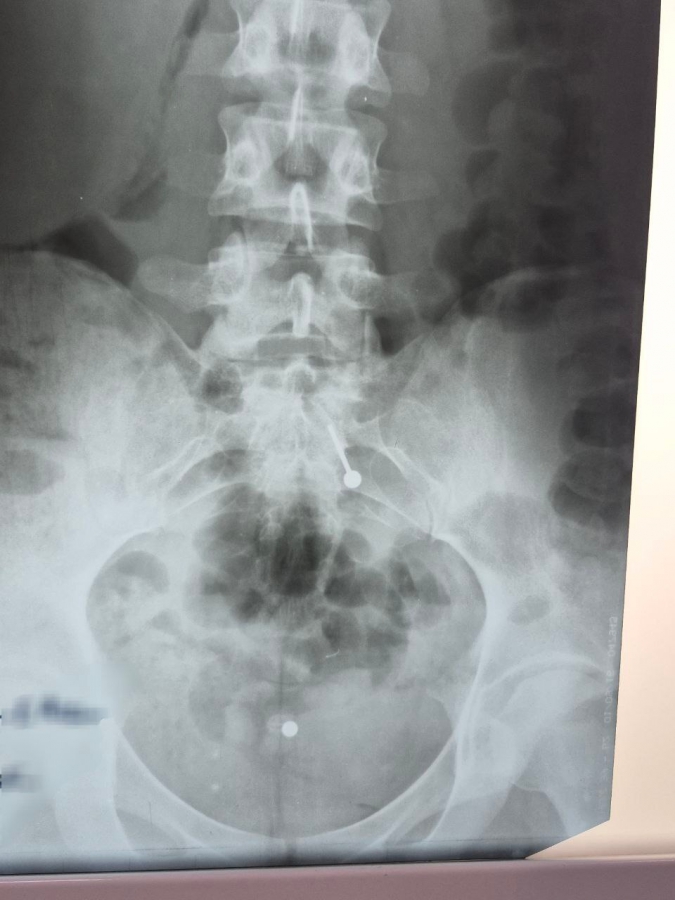

Девушка обратилась в стационар не сразу, а когда раскрутившиеся металлические части (шарик и штанга) уже покинули желудок и переместились в тонкий кишечник. Это сделало эндоскопическое извлечение без рисков осложнений невозможным.

Во втором случае в стационар попал двухлетний малыш, который, со слов мамы, примерно за час до обращения проглотил саморез. При каких условиях произошел инцидент, выяснить не удалось. Рентген подтвердил наличие острого металлического предмета внутри ребенка.

Саморез, к счастью, расположился шляпкой вниз, а острой частью вверх, что позволило предотвратить повреждение стенок желудочно-кишечного тракта и слизистой желудка. Благодаря этому удалось избежать необходимости проведения сложного открытого оперативного вмешательства. Мама ребенка отказалась от дальнейшей госпитализации, а малыш выписан под амбулаторное наблюдение. Саморез теперь войдет в коллекцию эндоскопистов больницы, в которой уже десятки самых необычных предметов.